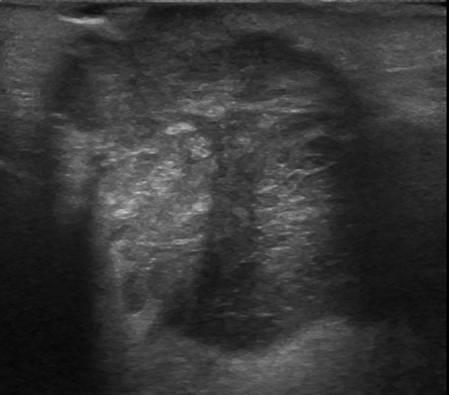

U tuyến nước bọt

» Thông tin: Nam giới – 79 tuổi.

» Lâm sàng: Khối vùng mang tai / K thực quản.

# Di căn tuyến nước bọt mang tai.